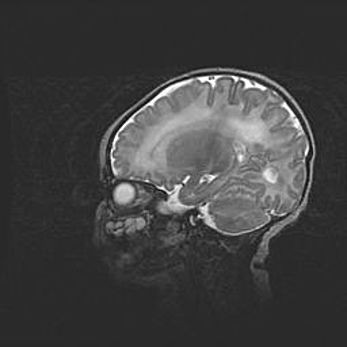

Церебральная ишемия II.

Возраст: 5 дней

Вес: 3400 г

Пол: женский

Окружность головы: 35 см

Срок гестации: 39 недель

Церебральная ишемия – это заболевание, характеризующееся недостаточностью (гипоксией) либо полным прекращением (аноксией) снабжения мозга кислородом по причине закупорки одного или нескольких сосудов. Это приводит к  что метаболическим расстройствам различной степени тяжести в тканях головного мозга, развитию коагуляционных некрозов и гибели нейронов.